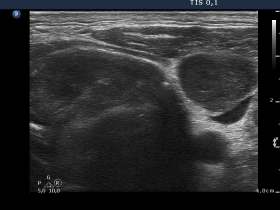

Palpation: a very hard mass involving the left thyroid and the left side of the neck. The mass was around 12 cm in maximal diameter.

Ultrasonography revealed that the palpable mass contained the enlarged left thyroid composed of a large hypoechogenic nodule with irregular borders and multiple irregular lymph nodes in the left side of the neck.

In such large nodules which occupies an entire lobe, we lack the clue on which we can decide whether a tumor extends beyond the thyroid or not.